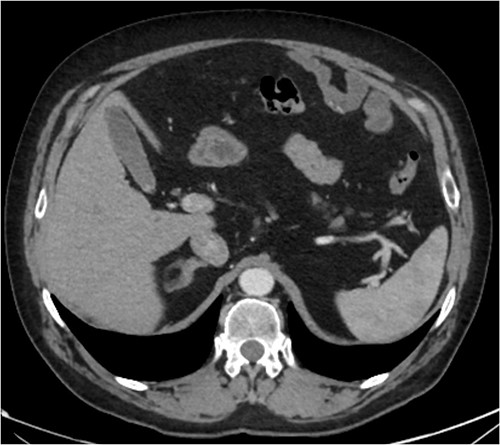

During admission the patient’s abdominal pain gradually improved, his Hb increased and he had no further coughing episodes. The patient was therefore stepped down to oral antibiotics and considered safe for discharge. A CT-AP four weeks post-discharge demonstrated a persisting 60 x 40 mm liquefying haematoma in the small bowel (Fig. 4), resolution of the peri-hepatic haematoma (Fig. 5) and interval reduction of the peri-splenic and pelvic haematomas. Given these improvements and the patient’s lack of significant symptoms, a plan to actively survey his progress was made.

Follow up CT angiogram showing improvement in mesenteric haematoma. Figure 4 is an axial section from the patient’s CT scan performed 4 weeks following discharge. The arrow highlights the patient’s liquefying mesenteric haematoma, which decreased from 104 x 62 mm to 60 x 40 mm. Combined with the improvement in the other areas of intra-abdominal bleeding and the patient’s overall clinical state, this image represents a significant improvement.

Follow up CT angiogram showing improvement in perihepatic haematoma. Figure 5 is another axial section from the patient’s CT angiogram performed 4 weeks following discharge and shows resolution of the perihepatic haematoma seen previously. Together with the other sections of the CT angiogram and the patient’s overall clinical state, the image represents a significant improvement in the patient’s intra-abdominal bleeding.